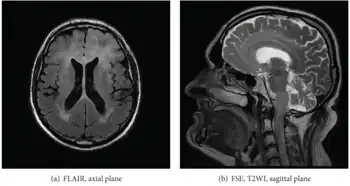

| Axial fluid-attenuated inversion recovery MRI image demonstrating tumor-related infiltration involving both temporal lobes (Short arrow), and the substantia nigra (Long arrow). | |

Before the advent of MRI, diagnosis was generally not established until autopsy. Even with MRI, however, diagnosis is difficult.[8] Typically, gliomatosis cerebri appears as a diffuse, poorly circumscribed, infiltrating non-enhancing lesion that is hyperintense on T2-weighted images and expands the cerebral white matter. It is difficult to distinguish from highly infiltrative anaplastic astrocytoma or GBM.